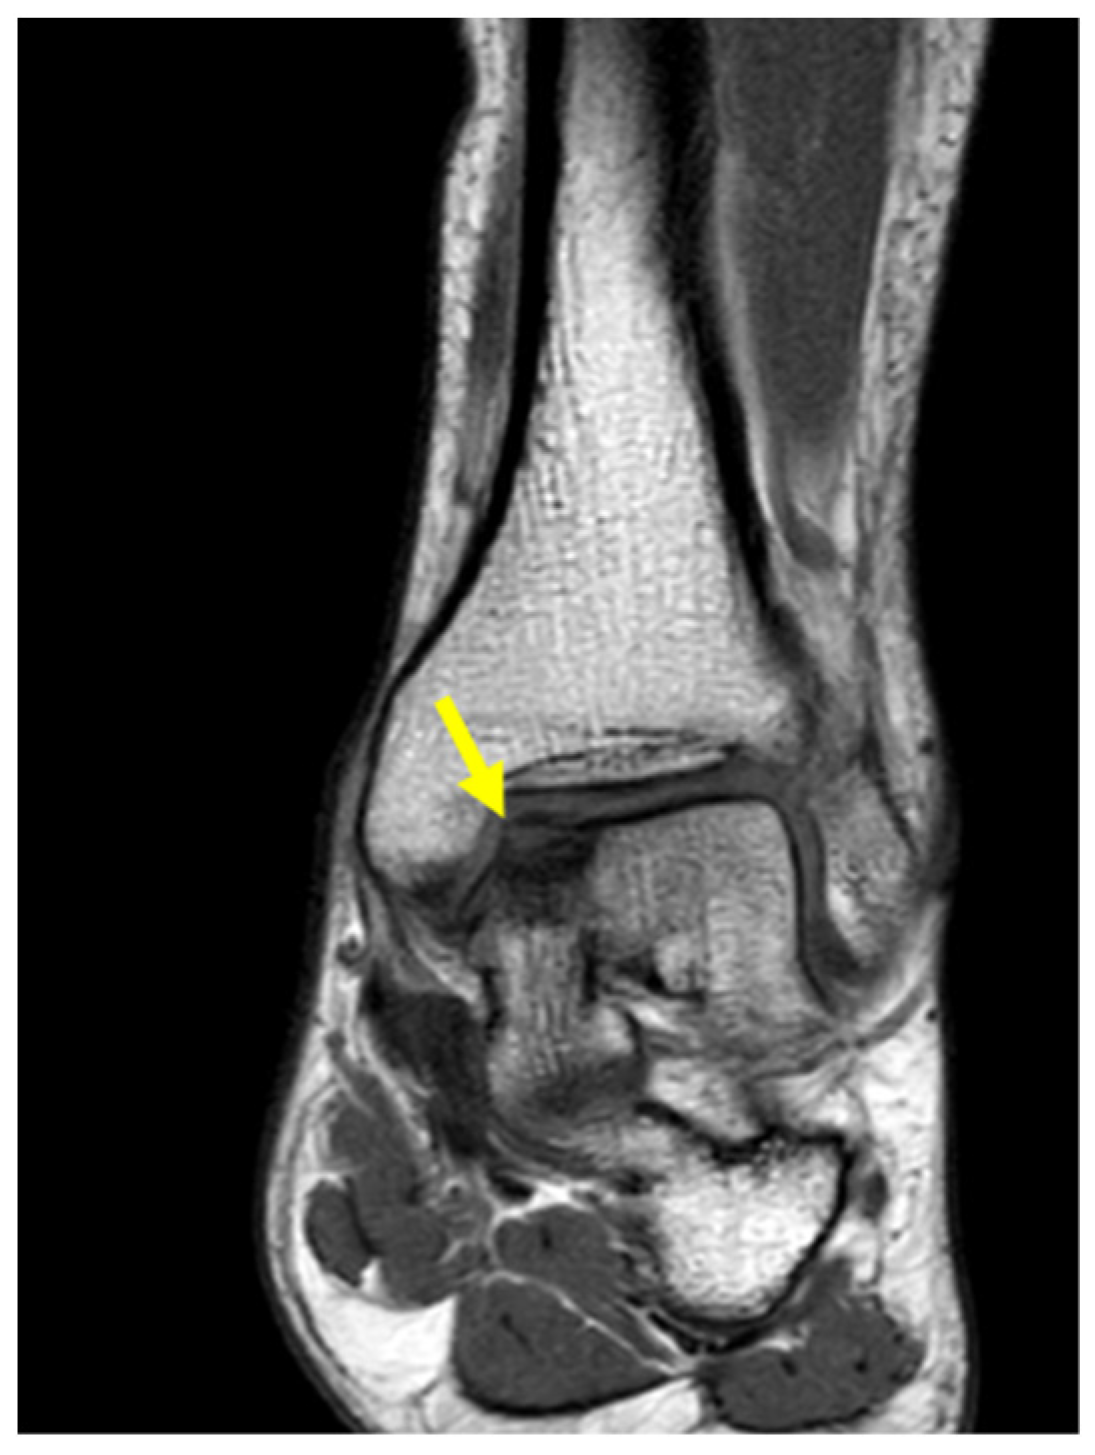

His left ankle was slightly swollen, painful to the touch on the antero-medial side. Tenderness was also reported at maximum degrees of ankle flexion and extension. Standard radiographic examinations have been performed, including antero-posterior and lateral weight-bearing views of the ankle, which showed some contour abnormalities, a subtle flattening, and an indistinct radiolucency above the cortical surface of the medial talar dome. Magnetic resonance imaging (MRI) found an OCD of 16 × 10 × 8 mm on the medial side of the left talus (Figure 1).

Figure 1. Coronal ankle MRI showing OCD (arrow) on the medial side of the left talus.